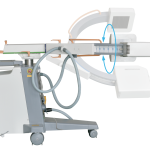

15) Orbital rotation(°): 150 (117/-33)

16) Lateral rotation(°): 360 (±225)

17) wig/wag(°): ±15